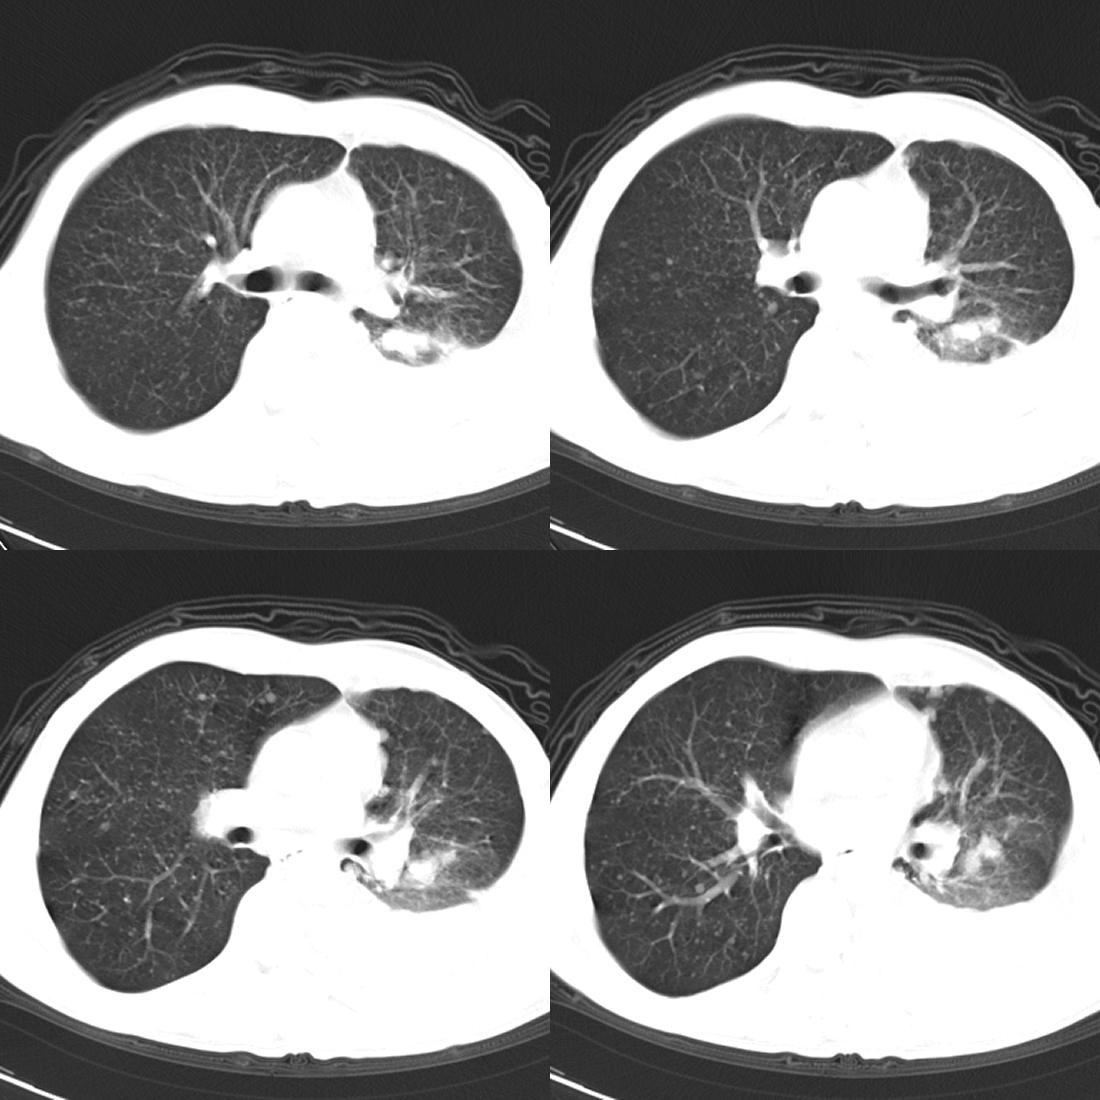

左肺上叶周围型肺癌伴肺\\胸膜\\肋骨\\胸椎横突转移,左侧胸腔积液.

左侧椎体、横突、肋骨呈溶骨性破坏,半左侧胸腔中等量积液;左肺尖部可见一肿块影,边界欠清;多考虑恶性骨肿瘤,不除外肺尖部转移性表现可能。

左肺没见明显占位病变,但左肺门增大,不除外肿大淋巴结,左侧肋骨、胸椎融骨性破坏,考虑左侧胸膜恶性病变

左肺上叶周围型肺癌伴双肺\\胸膜\\肋骨\\胸椎横突转移,左侧胸腔积液.

关注中 左上肺应该有个包快吧,还有左肺是部分不张